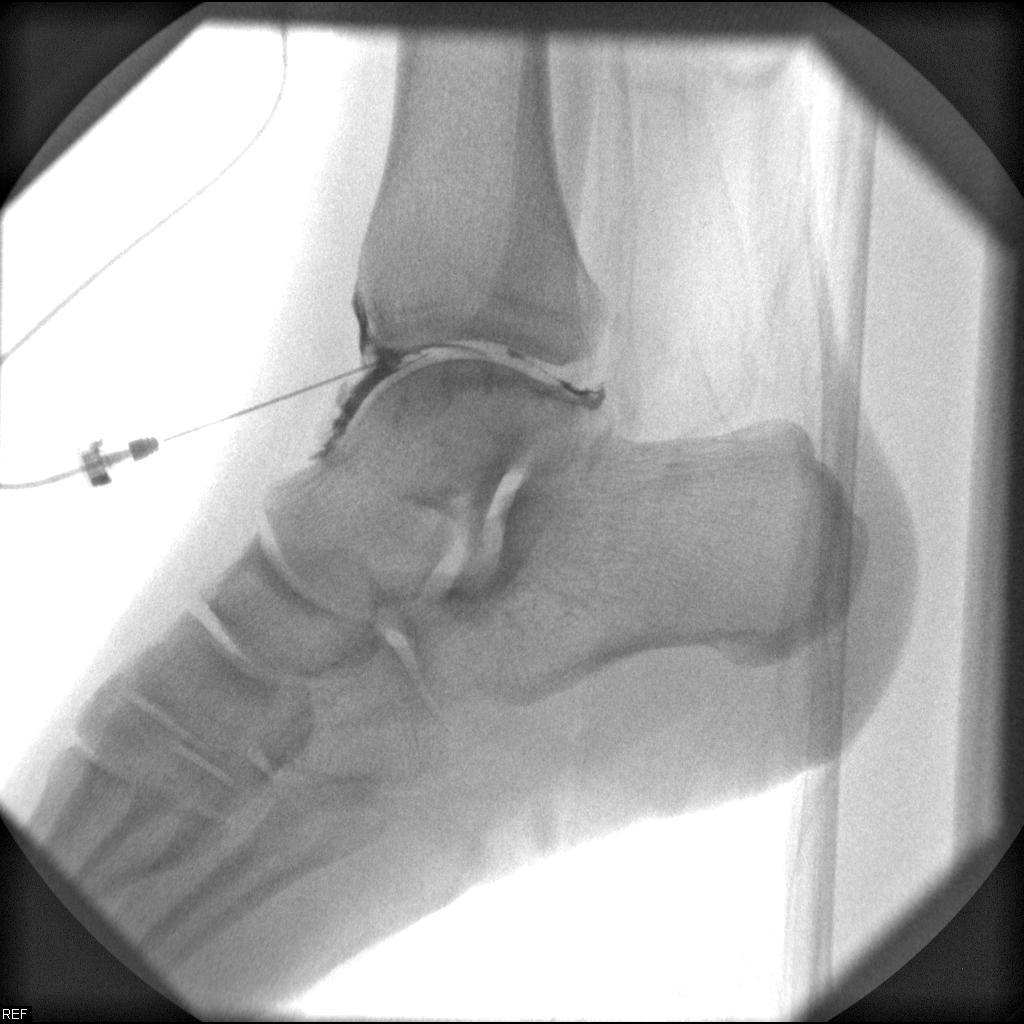

Fluoroscopy - Joint Injections

Fluoroscopy is a study of moving body structures--similar to an X-ray "movie." A continuous X-ray beam is passed through the body part being examined. The beam is transmitted to a TV-like monitor so that the body part and its motion can be seen in detail. Fluoroscopy, as an imaging tool, enables physicians to look at many body systems, including the skeletal, digestive, urinary, respiratory, and reproductive systems.

Painful joints can be visualised with x-ray and treated under fluoroscopic guidance. Cortisone shots are most commonly given into joints, such as your elbow, hip, ankle, knee, shoulder and wrist. Even the small joints in your hands and feet may benefit from these injections.

The area around the injection site will be cleaned and an image of your joint will be taken, so that the radiologist knows exactly where to administer the medication. You will likely feel some pressure when the needle is inserted.